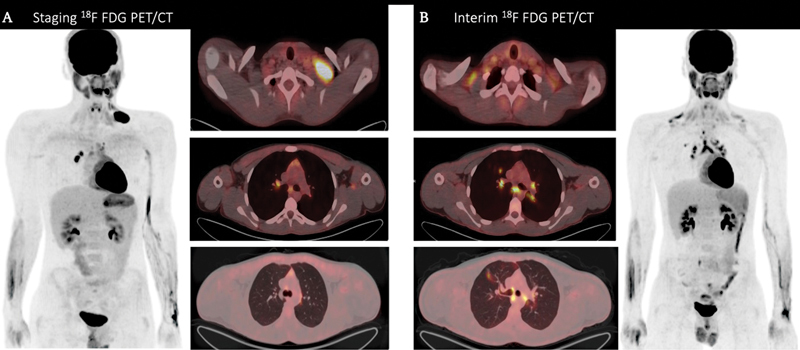

肉样瘤病经常与各种血液肿瘤和实体瘤相关;它可能在肿瘤评估时偶然被发现。肉样瘤病可能发生在某些癌症之前,也可能与其他癌症并存,或在 1 到 2 年后才被诊断出来。对于组织病理学确诊为霍奇金淋巴瘤并正在接受氟脱氧葡萄糖-正电子发射计算机断层扫描(FDG-PET/CT)评估的患者来说,影响肺门淋巴结和纵隔淋巴结的肉样瘤反应会给诊断带来挑战,因为肉样瘤反应不易与淋巴瘤浸润区分开来。如果淋巴瘤化疗后的随访 FDG-PET/CT 扫描中出现明显的活动性增加或持续存在,且与主要确诊淋巴瘤疾病部位的完全代谢反应相关联,则高度提示并发肉样瘤病,有必要进行仔细评估,以避免不必要的治疗。

Sarcoidosis is frequently associated with various hematological and solid tumors; it can be discovered by chance during tumor evaluations. Sarcoidosis can occur before some cancers, coexist with others, or be diagnosed 1 to 2 years later. Sarcoid reaction affecting hilar and mediastinal lymph nodes can pose a diagnostic challenge in patients with histopathological confirmation of Hodgkin lymphoma who are being evaluated using fluorodeoxyglucose-positron emission tomography computed tomography (FDG-PET/CT) scan because it cannot be easily distinguished from lymphoma infiltration. The presence of an increase or persistence of a prominent activity on a follow-up FDG-PET/CT scan after chemotherapy treatment for lymphoma that is associated with a complete metabolic response in the site of the primarily diagnosed lymphomatous disease is highly suggestive of concurrent sarcoidosis and necessitates careful assessment to avoid unnecessary therapy.